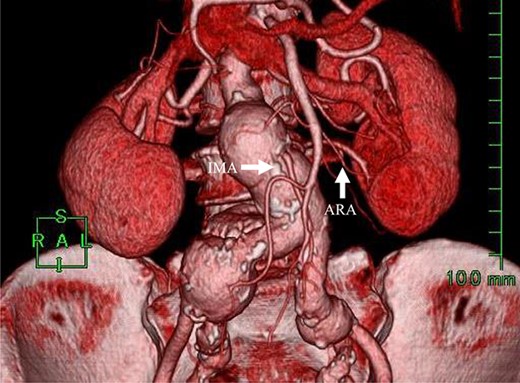

A 70-year-old female with a medical history of hypertension and dyslipidemia underwent EVAR for a 37 mm right common iliac artery aneurysm (CIAA). Preoperative imaging revealed that she also had small AAA (35 mm) and left CIAA (24 mm) (Fig. 1). In addition, she had a patent IMA and left ARA from the AAA sac. Stent-grafts were deployed in the right CIAA with right internal iliac artery embolization and the small AAA covering the IMA and the left ARA without embolization. A flared stent-graft leg was placed in the left CIAA at that time. Although postoperative CT showed a type II endoleak from the IMA, no enlargement of the AAA was observed by annual CT or ultrasound examination for 4 years after EVAR. However, during the next 3 years, the AAA and the left CIAA gradually enlarged to 50 mm and 35 mm, respectively.

Preoperative CT angiography revealed that the IMA and ARA branched closely from the sac.